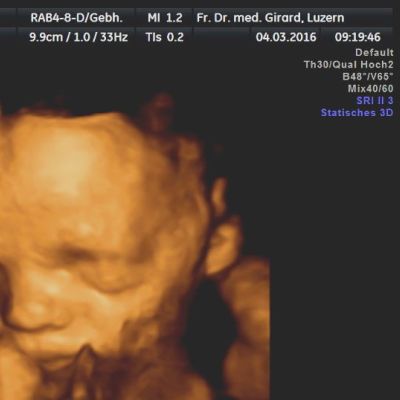

Im dritten Trimester

(30 – 34 SSW)

steht das kindliche Wachstum im Vordergrund. Ein normal grosses Kind und eine normale Fruchtwasser-Menge sprechen für eine normale Funktion der Plazenta. Auch die Lage des Kindes in der Gebärmutter gewinnt zunehmend an Bedeutung, sollte sich das Kind doch gegen den Geburts-Termin in eine Schädellage drehen. Zudem können einige Fehlbildungen des Kindes, die für die optimale Betreuung des Kindes nach der Geburt von Bedeutung sein können, erst in diesem späten Schwangerschafts-Alter erfasst werden.